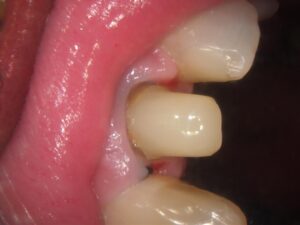

技工士が直接お口の中を確認(立ち会い)することで、隣の歯の色味や透明感、表面の細かな凹凸を正確に把握できます。写真だけでは伝わりにくいニュアンスを反映できるため、「どこを治療したかわからない」ほど自然な仕上がりが可能になります。

当院では被せ物の治療の際に、型取りの写真の共有や技工士さんの立会いを行うことで

より精度の高い被せ物を入れる取り組みをしています。